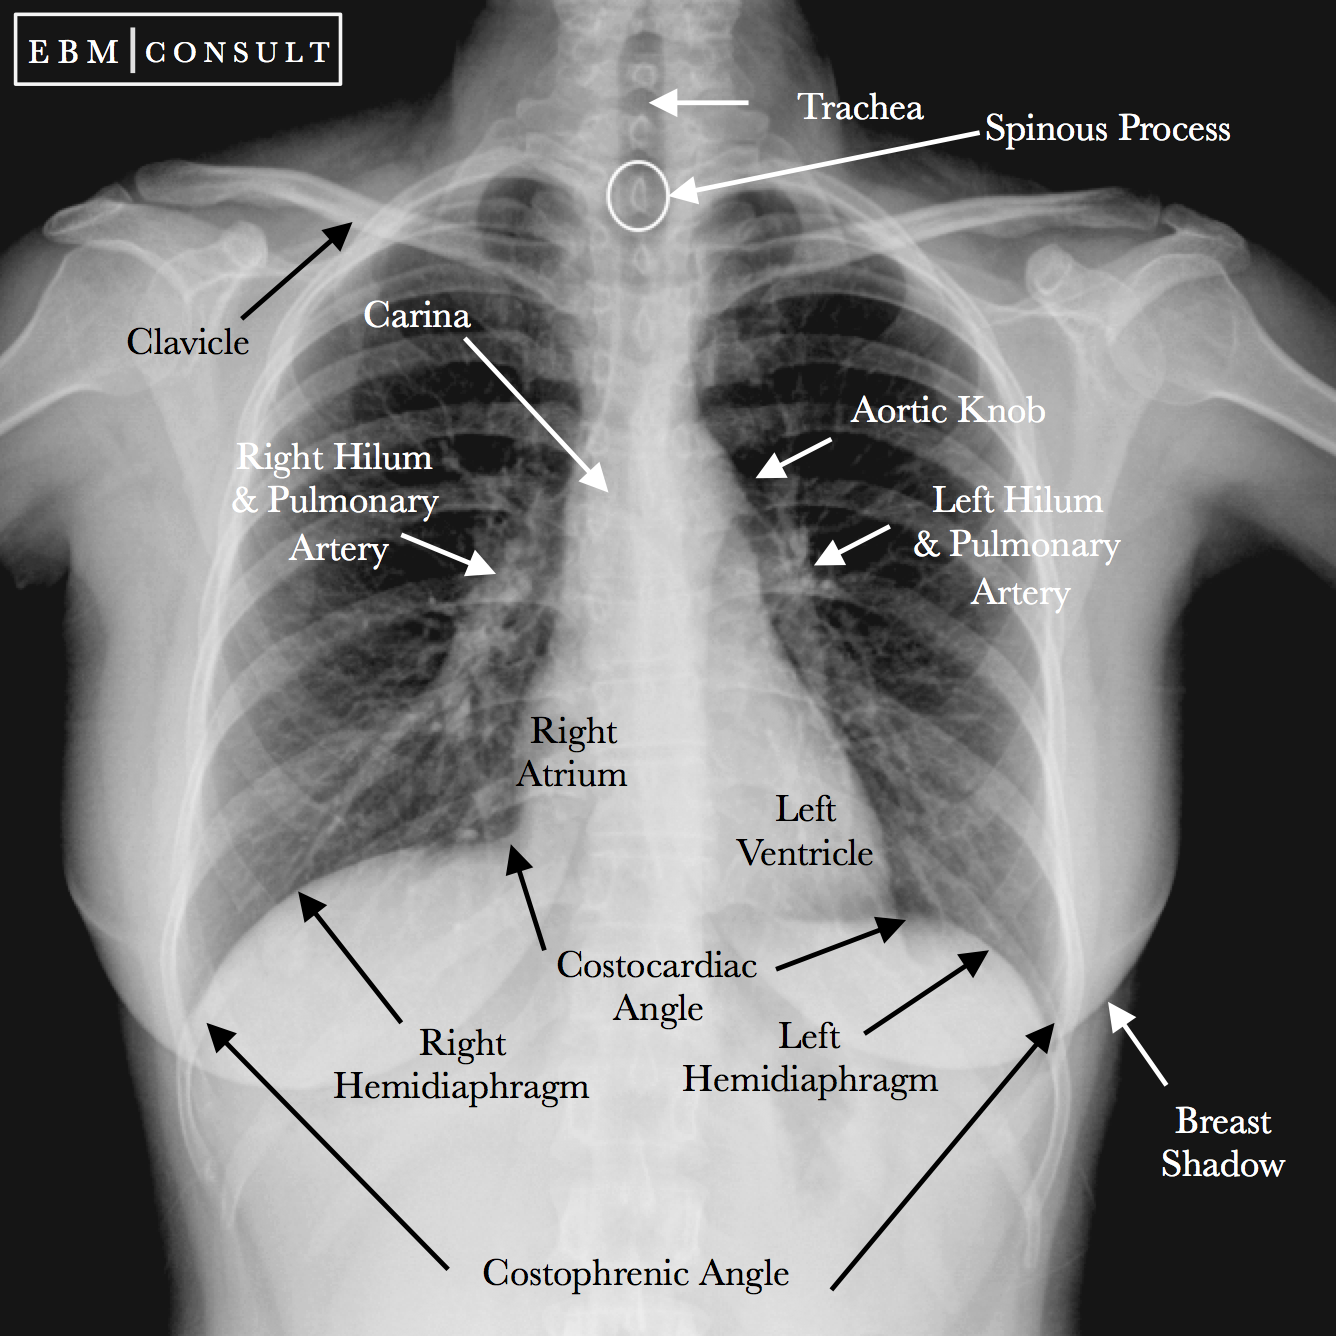

Trachea

A structure seen on chest X-ray that represents the airway.

Hila

Areas on a chest X-ray where the lungs' blood vessels enter and exit.

Diaphragm

The muscle seen on chest X-ray that separates the thoracic and abdominal cavities.

Aortic Knob

The curved appearance of the aorta as seen in chest imaging.

Cardiac Contours

Since we are looking at shadows (knowing the heart is soft tissue density), the silhouette of the heart demonstrates certain contours

Aorta – knob on frontal view

PA – vascular so visible, unlike bronchus; left main sits higher than right

Right and left atria – right atria makes up right heart border; left atria will enlarge superior portion of left heart border

LV – posterior structure; more prominent filling retrocardiac space on lateral

Descending aorta disappears because it is buried in mediastinal soft tissue densities